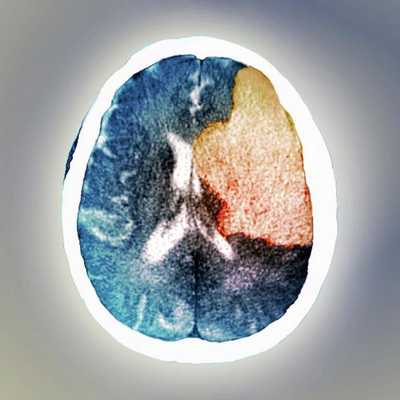

Современной медициной бредовое расстройство рассматривается как расстройство головного мозга. В пользу этого говорит тот факт, что бредовые идеи могут развиваться вследствие токсических или метаболических нарушений, нейродегенеративных заболеваний (связанных с гибелью нервных клеток), опухолей или инсультов. В таком случае бредовые идеи будут называться вторичными, так как они развиваются на фоне другой (основной) болезни.

Ряд клинических исследований, изучавших органические психозы у пациентов с очаговыми инсультами, а затем новейшие нейровизуализационные исследованиях пациентов с бредовыми идеями, выявили критическую роль правой латеральной префронтальной коры в развитии бреда [6] .

Анализ клинических случаев пациентов с очаговыми инсультами показал, что бред развивается после одностороннего повреждения правого полушария мозга. Однако при этом у большинства пациентов с инсультом в правом полушарии бредовое расстройство всё же не развивалось. Уже позже благодаря расширенному анализу нейровизуализационных исследований стало известно, что бредовые идеи у людей с очаговым инсультом связаны именно с поражением правой латеральной префронтальной коры или её областью.